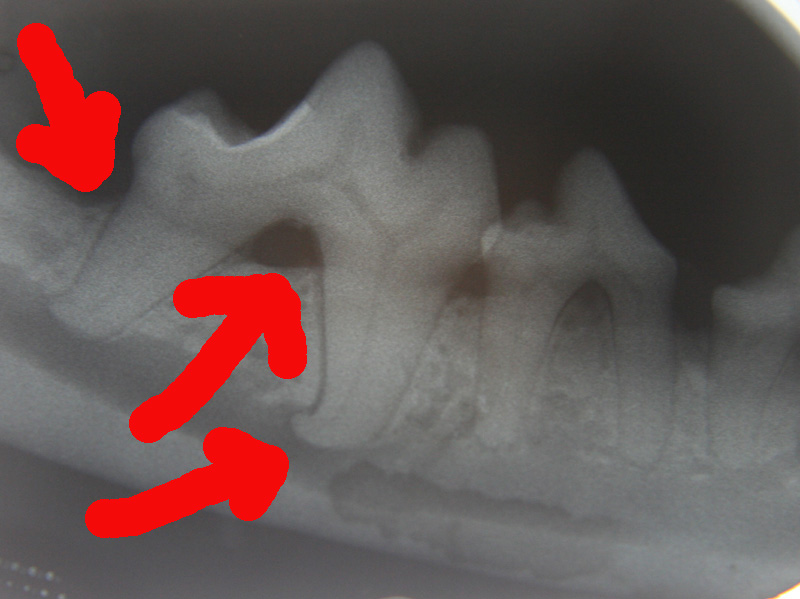

Dog Dental Bone Loss . These are signs of infection in the mouth, and they mean a vet visit is needed. horizontal or vertical alveolar bone loss may be seen radiographically. These include diseases of the teeth, gums, tongue, bones, and other structures of the mouth. once the dog is anesthetized, a dental probe is used to measure loss of attachment around each tooth. Early periodontitis is characterized by a 25% loss of the tooth’s attachment to supporting structures. Dental decay is painful, and you may notice your dog has smelly breath, reduced appetite or eating on one side, drooling, missing teeth, or bleeding gums. In early periodontitis, 0% to 30% bone loss. The supporting structures around the canine's teeth are still intact at this point. While some types of dental disease are due to bacterial infections, trauma may also cause dental disease due to tooth fractures and even jaw fractures. These are usually recommended as a. periodontal disease is inflammation of some or all of a tooth's support. there’s also evidence of more than 50 percent of bone support loss. Gingivitis (infection of the gums) presents with mild redness and swelling. Tartar buildup might also be apparent in some areas. dental disease refers to any abnormalities that occur in your dog’s mouth.

These are signs of infection in the mouth, and they mean a vet visit is needed. Tartar buildup might also be apparent in some areas. Gingivitis (infection of the gums) presents with mild redness and swelling. periodontal disease is inflammation of some or all of a tooth's support. The supporting structures around the canine's teeth are still intact at this point. Early periodontitis is characterized by a 25% loss of the tooth’s attachment to supporting structures. These are usually recommended as a. horizontal or vertical alveolar bone loss may be seen radiographically. In early periodontitis, 0% to 30% bone loss. once the dog is anesthetized, a dental probe is used to measure loss of attachment around each tooth.

Dog Dental Bone Loss once the dog is anesthetized, a dental probe is used to measure loss of attachment around each tooth. The supporting structures around the canine's teeth are still intact at this point. once the dog is anesthetized, a dental probe is used to measure loss of attachment around each tooth. horizontal or vertical alveolar bone loss may be seen radiographically. there’s also evidence of more than 50 percent of bone support loss. These include diseases of the teeth, gums, tongue, bones, and other structures of the mouth. periodontal disease is inflammation of some or all of a tooth's support. Early periodontitis is characterized by a 25% loss of the tooth’s attachment to supporting structures. dental disease refers to any abnormalities that occur in your dog’s mouth. Tartar buildup might also be apparent in some areas. While some types of dental disease are due to bacterial infections, trauma may also cause dental disease due to tooth fractures and even jaw fractures. These are signs of infection in the mouth, and they mean a vet visit is needed. Dental decay is painful, and you may notice your dog has smelly breath, reduced appetite or eating on one side, drooling, missing teeth, or bleeding gums. Gingivitis (infection of the gums) presents with mild redness and swelling. In early periodontitis, 0% to 30% bone loss. These are usually recommended as a.